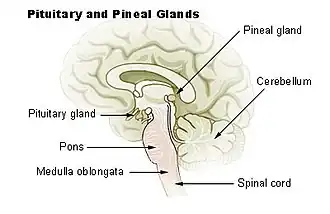

Diagram of pituitary and pineal glands in the human brain | |

The pineal gland (also known as the pineal body[1] or epiphysis cerebri) is a small endocrine gland in the brain of most vertebrates. It produces melatonin, a serotonin-derived hormone, which modulates sleep patterns following the diurnal cycles.[2] The shape of the gland resembles a pine cone, which gives it its name.[3] The pineal gland is located in the epithalamus, near the center of the brain, between the two hemispheres, tucked in a groove where the two halves of the thalamus join.[4][5] It is one of the neuroendocrine secretory circumventricular organs in which capillaries are mostly permeable to solutes in the blood.[6]

The pineal gland is a pine cone-shaped (hence the name), unpaired midline brain structure.[3][9] It is reddish-gray in colour and about the size of a grain of rice (5–8 mm) in humans. It forms part of the epithalamus.[1] It is attached to the rest of the brain by a pineal stalk.[10] The ventral lamina of the pineal stalk is continuous with the posterior commissure, and its dorsal lamina with the habenular commissure.[10]

Location

It normally lies in a depression between the two superior colliculi.[10] It is situated between the laterally positioned thalamic bodies, and posterior to the habenular commissure. It is located in the quadrigeminal cistern.[1] It is located posterior to the third ventricle and encloses the small, cerebrospinal fluid-filled pineal recess of the third ventricle which projects into the stalk of the gland.[11]

Unlike most of the mammalian brain, the pineal gland is not isolated from the body by the blood–brain barrier system;[12] it has profuse blood flow, second only to the kidney,[13] supplied from the choroidal branches of the posterior cerebral artery.